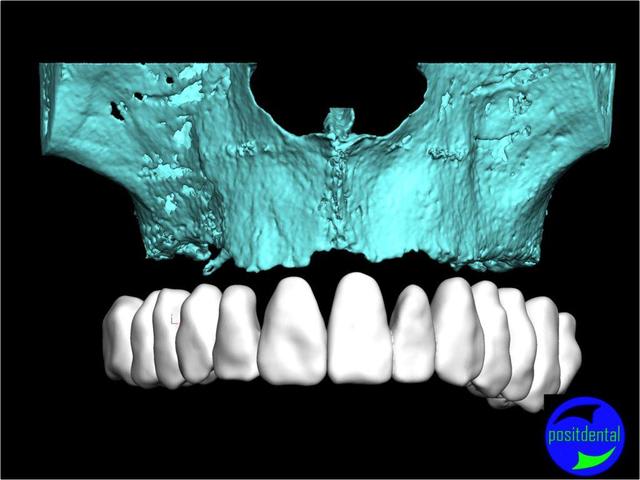

Posit fait une étude pour démontrer la faisabilité de son système, et honnêtement sa démarche semble intéressante, et provoque une réflexion sympa chez D57 et moi même.

La solution unique n'existant pas il est très intéressante que nous échangions nos différents points de vue.

La solution sera une expansion, (what else?) mais dirigée du point de vue prothésiste pour la partie mécanique, ce qui devrait être plus sécurisant pour le patient, et constructif pour nous tous.

une autre vue du photshopman:

modèle stéréo du à la gentillesse de Posit